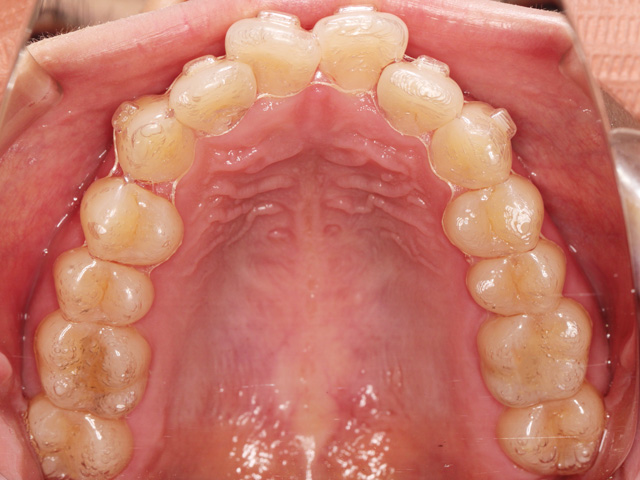

上顎の画像です。前歯のスペースが不足しています。

中切歯が押し出されているように見える状態です。また右上の中切歯は専門用語で「捻転(ねんてん)」と呼ばれる、歯が捻じれている状態です。

正中の中心に向かって捻じれている「近心捻転(きんしんねんてん)」と呼ばれる状態です。